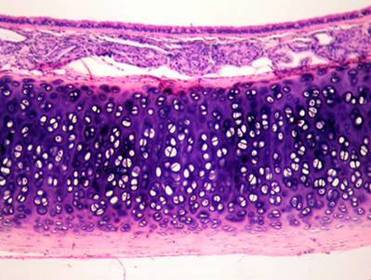

Caption: : Epitelio respiratorio: Cilindrico ciliado pseudoestratificado con celulas caliciformes

Epitelio respiratorio

Células caliciformes : 30% Secretan mucina RER y Golgi desarrollado Células ciliadas cilindricas: 30% 300 cilios aprox en la superficie apical Los cilios se mueven hacia la faringe recogiendo partículas para ser deglutidos o expectorados Células basales: 30% No llegan a la superficie Se dividen continuamente por mitosis  Dan origen a los demás tipos celulares

Celulas cilindricas con microvellosidades: 3% Tipo1: Expansiones en su base, receptor sensitivo Tipo2: Células inmaduras o células caliciformes agotadas Células basales con gránulos o células de Kulchitsky: 3% Necesitan tinción especial Pertenecen al Sitema neuroendocrino difuso o Sistema APUD Liberan serotonina, calcitonina, catecolaminas virtiendolas  a  la sangre. Células basales serosas: 3%Células cúbicas que secretan proteínas